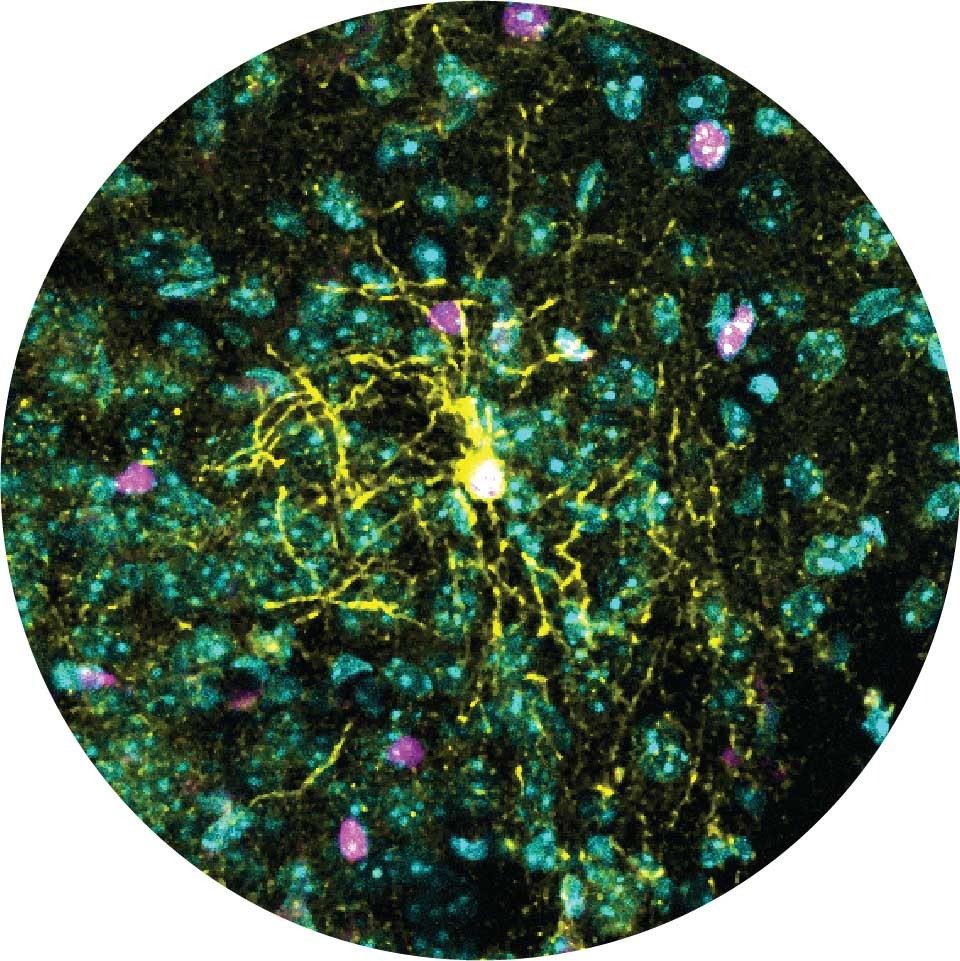

Новое исследование ученых из Научного института Вейцмана раскрывает беспрецедентные подробности того, как подкатегория клеток мозга самцов и самок мышей по-разному реагирует на стресс. Сообщается, что полученные результаты могут привести к лучшему пониманию и лечению тревоги, депрессии и даже ожирения.

Ученые из лаборатории профессора Алона Чена в Институте Вейцмана, которая специализируется на изучении реакции организмов на стресс, пишут: «Мы направили наиболее чувствительную исследовательскую линзу на область мозга, которая действует как центральный узел стрессовой реакции у млекопитающих, - паравентрикулярное ядро (PVN) гипоталамуса», — объяснила доктор Елена Бривио.